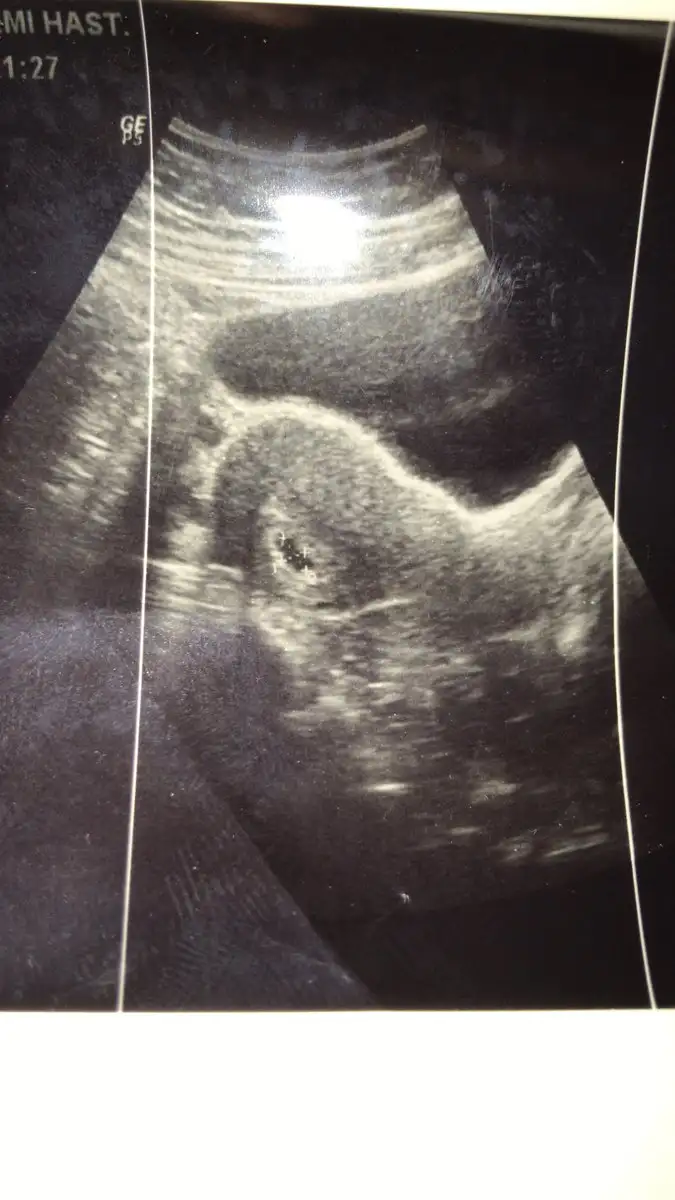

Kızlarrr merhabaaa :) bende yeni gebeyım dün doktora gittik 5 hafta 2günlük kese nasıl görünüyor

Eklentiler

• 0B810A6D-9369-4FE0-B699-22348EB0C413.webp

0B810A6D-9369-4FE0-B699-22348EB0C413.webp

36 KB · Görüntüleme: 52